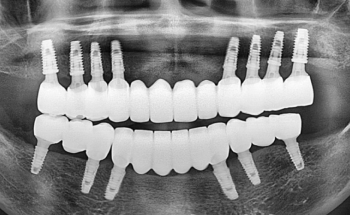

틀니 대신 전체임플란트를 선택하는 이유

무치악에서 전체임플란트로 회복한 사례